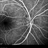

- high watermark, neuroretinitis

- Tom Steele, CRA Midwest Eye Institute, Indianapolis Indiana

Scanning laser ophthalmoscope

Heidelberg Spectralis - Description

- 28 year-old Caucasian male, presented with blurry vision OD for over 3 months.